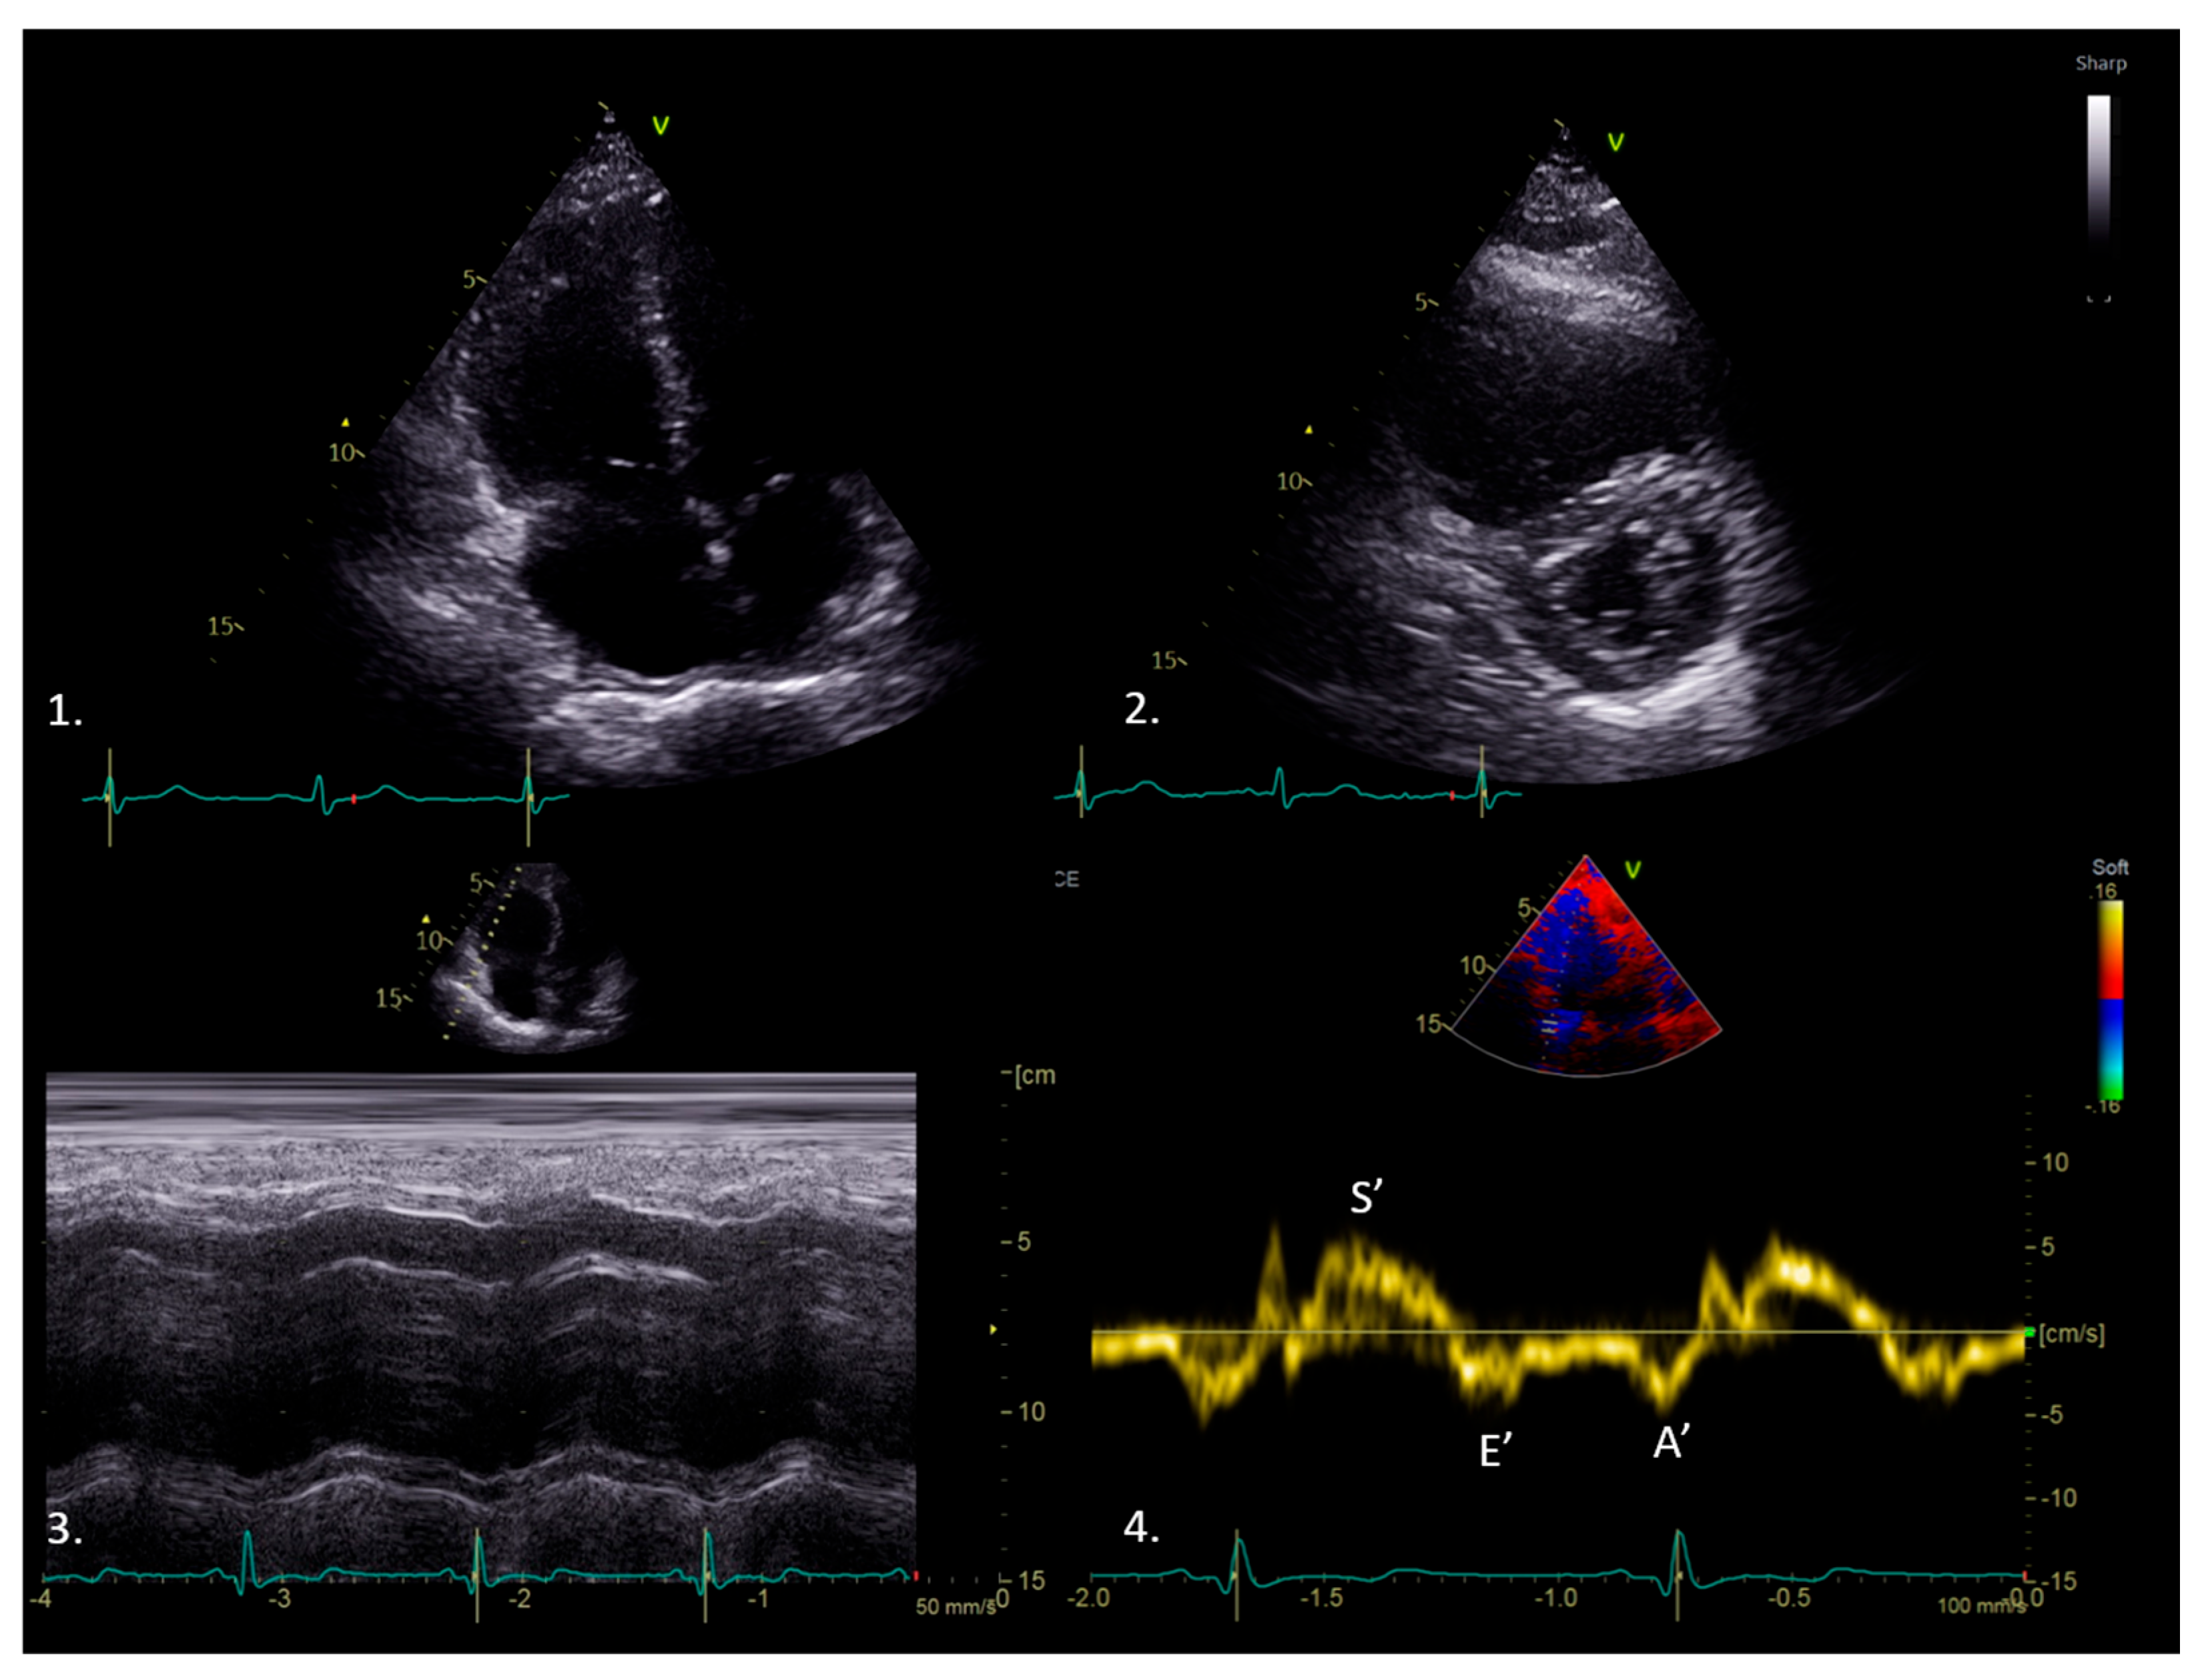

3. Tissue Doppler Imaging Characteristics

10. TDI in Constrictive Pericarditis